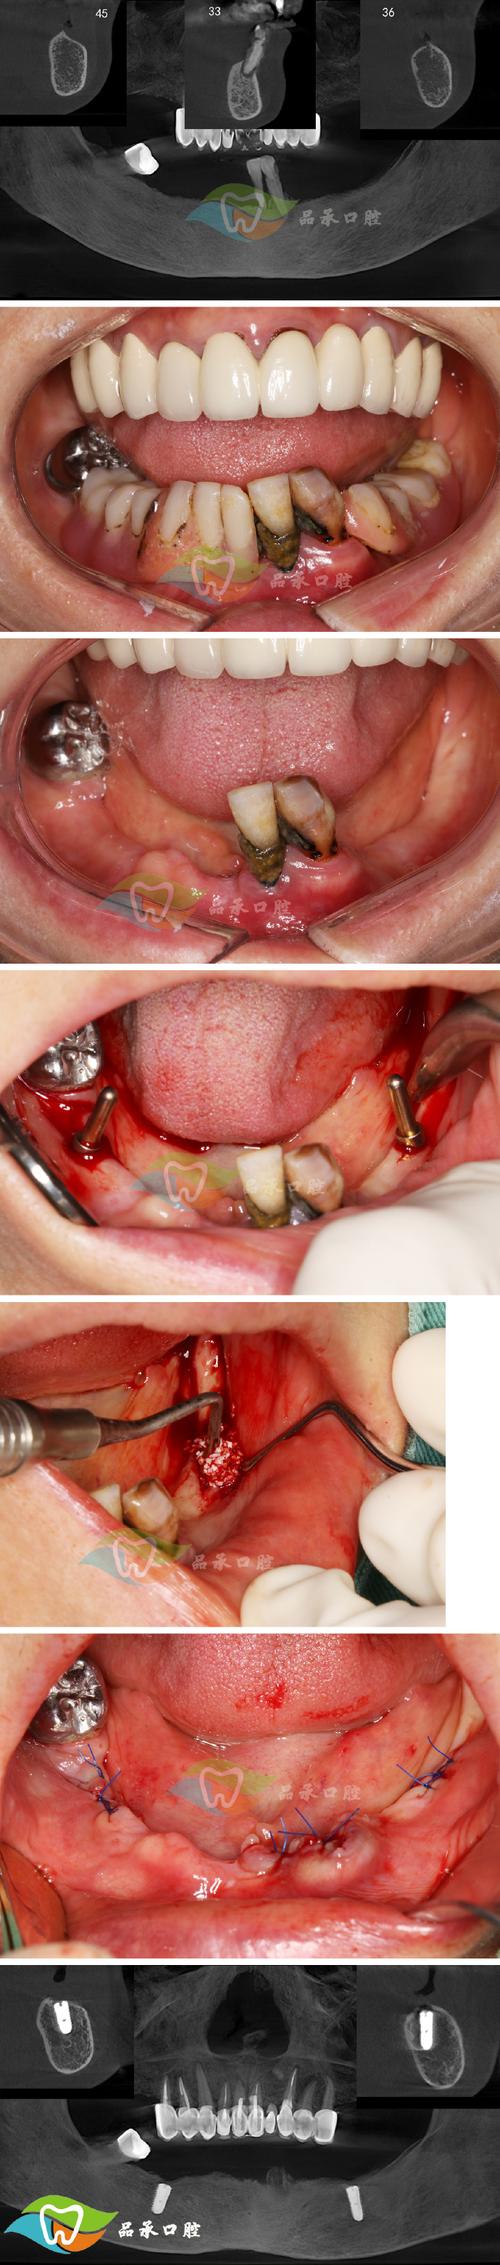

种植体周围炎:

- 原因: 这是种植体周围软硬组织的慢性炎症,类似于天然牙的牙周炎,主要原因是口腔卫生维护不当导致菌斑堆积,刺激炎症反应,进而破坏支撑种植体的牙槽骨。

- 症状: 种植体周围牙龈红肿、出血、溢脓、牙周袋形成、种植体周围骨吸收、种植体松动。

- 处理: 强调预防为主!一旦发生,治疗难度大,包括专业的机械清创(刮治)、激光治疗、必要时手术翻瓣清创、骨增量等,严重时可能需要取出种植体。

- 预防: 患者终身良好的口腔卫生习惯是关键! 正确使用牙线、牙缝刷、冲牙器等,并定期(至少每年1-2次)进行专业的种植体维护(洁治和刮治)。

骨结合失败(种植体松动或脱落):

(图片来源网络,侵删)- 原因: 骨结合失败指种植体未能与牙槽骨牢固融合,可能原因包括:手术创伤过大、感染、过早负重、吸烟、严重糖尿病、骨质疏松(未经治疗或管理不佳)、放疗史、局部骨量严重不足、咬合力过大或异常(咬合创伤)、材料过敏(罕见)等。

- 症状: 种植体在愈合期或使用期出现松动、脱落、咀嚼时疼痛。

- 处理: 一旦确诊失败,通常需要取出种植体,待伤口愈合后(通常3-6个月)再考虑重新种植。